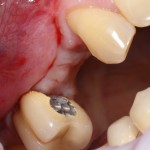

Затем устанавливаем имплантат. В данном случае, Friadent XiVE. Диаметром 3,4 мм — это минимальный размер импланта, который можно использовать в эстетически значимой зоне:

Не обращаем внимания ни на стабильность импланта, ни на объемы окружающей костной ткани. Имплантат после установки может крутиться, шататься и вращаться — правило, когда первичная стабильность была главным условием успешной имплантации, применимо лишь ко второму этапу развития имплантологии. Более того, друзья, есть импланты, которые вообще не предполагают первичной стабильности. Например, Bicon.

Очень хочется использовать имплантат поменьше диаметром (3.0 мм), но, как я уже отметил, минимальный размер в эстетически значимой зоне — 3,4 мм. Связано это с тем, что на импланты диаметром 3.0 мм выпускается очень небольшое количество супраструктур (абатментов), поэтому в дальнейшем можно столкнуться со сложностями при протезировании.